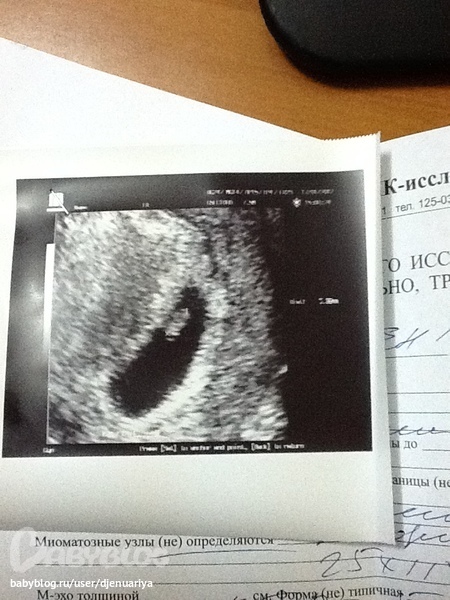

Не верю своим глазам!!! Сделав таких тестов штук 8, я решила больше не мучать себя и и пойти в инвитро сдать кровь на хгч. В тот же вечер мне на почту приходит результат 3392, что соответствовало 5 акушерским неделям!!!!!!!! И спустя несколько дней я иду на узи, чтобы подтвердить маточную Б. В итоге: после узи в платной клинике и диагнозом замершая беременность(нет сердцебиения), я со слезами на глазах еле доехала домой...

На выскабливание не решилась, думаю подожду недельку и поеду в другую клинику. Эта неделя была для меня адом. Но спасибо Богу, что я так поступила!!!! 17 января была на узи в другой клинике, где мне показали моего кроху и пульсирующую клеточку - сердечко))))))